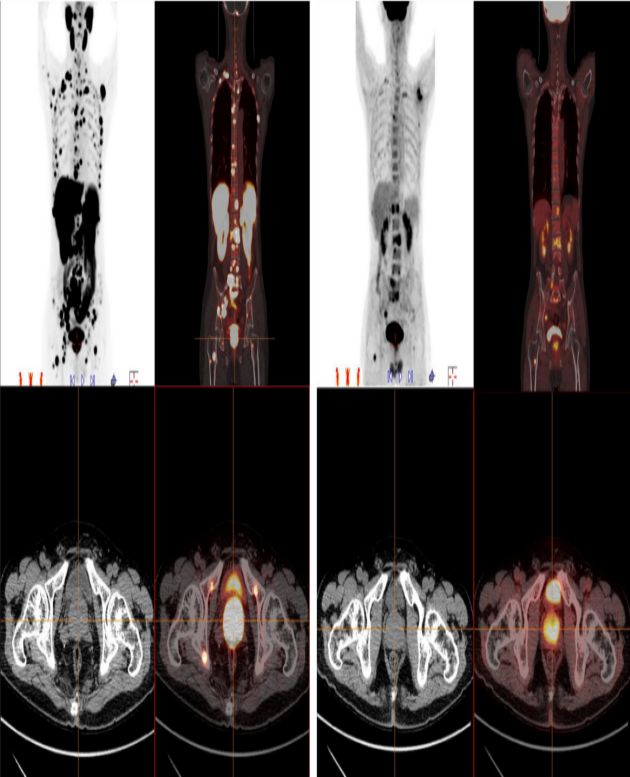

患者,中年男性,体检发现血清PSA水平高于100ng/ml,在我科分别行18F-PSMA-1007 PET/CT(图1)和18F-FDG PET/CT(图2)检查,该患者最终诊断为前列腺癌伴腹盆腔淋巴结及全身多处骨转移。如图所示, 18F-PSMA-1007 PET/CT 发现的转移灶远远多于-FDG PET/CT 检查所发现的, 对前列腺癌原发灶及转移灶的探测要明显优于F-FDG PET/CT,尤其对于早期发现微小转移灶具有明显的优势(如图:骨盆骨多处小结节样骨转移灶在F-FDG PET/CT上表现不明显)。